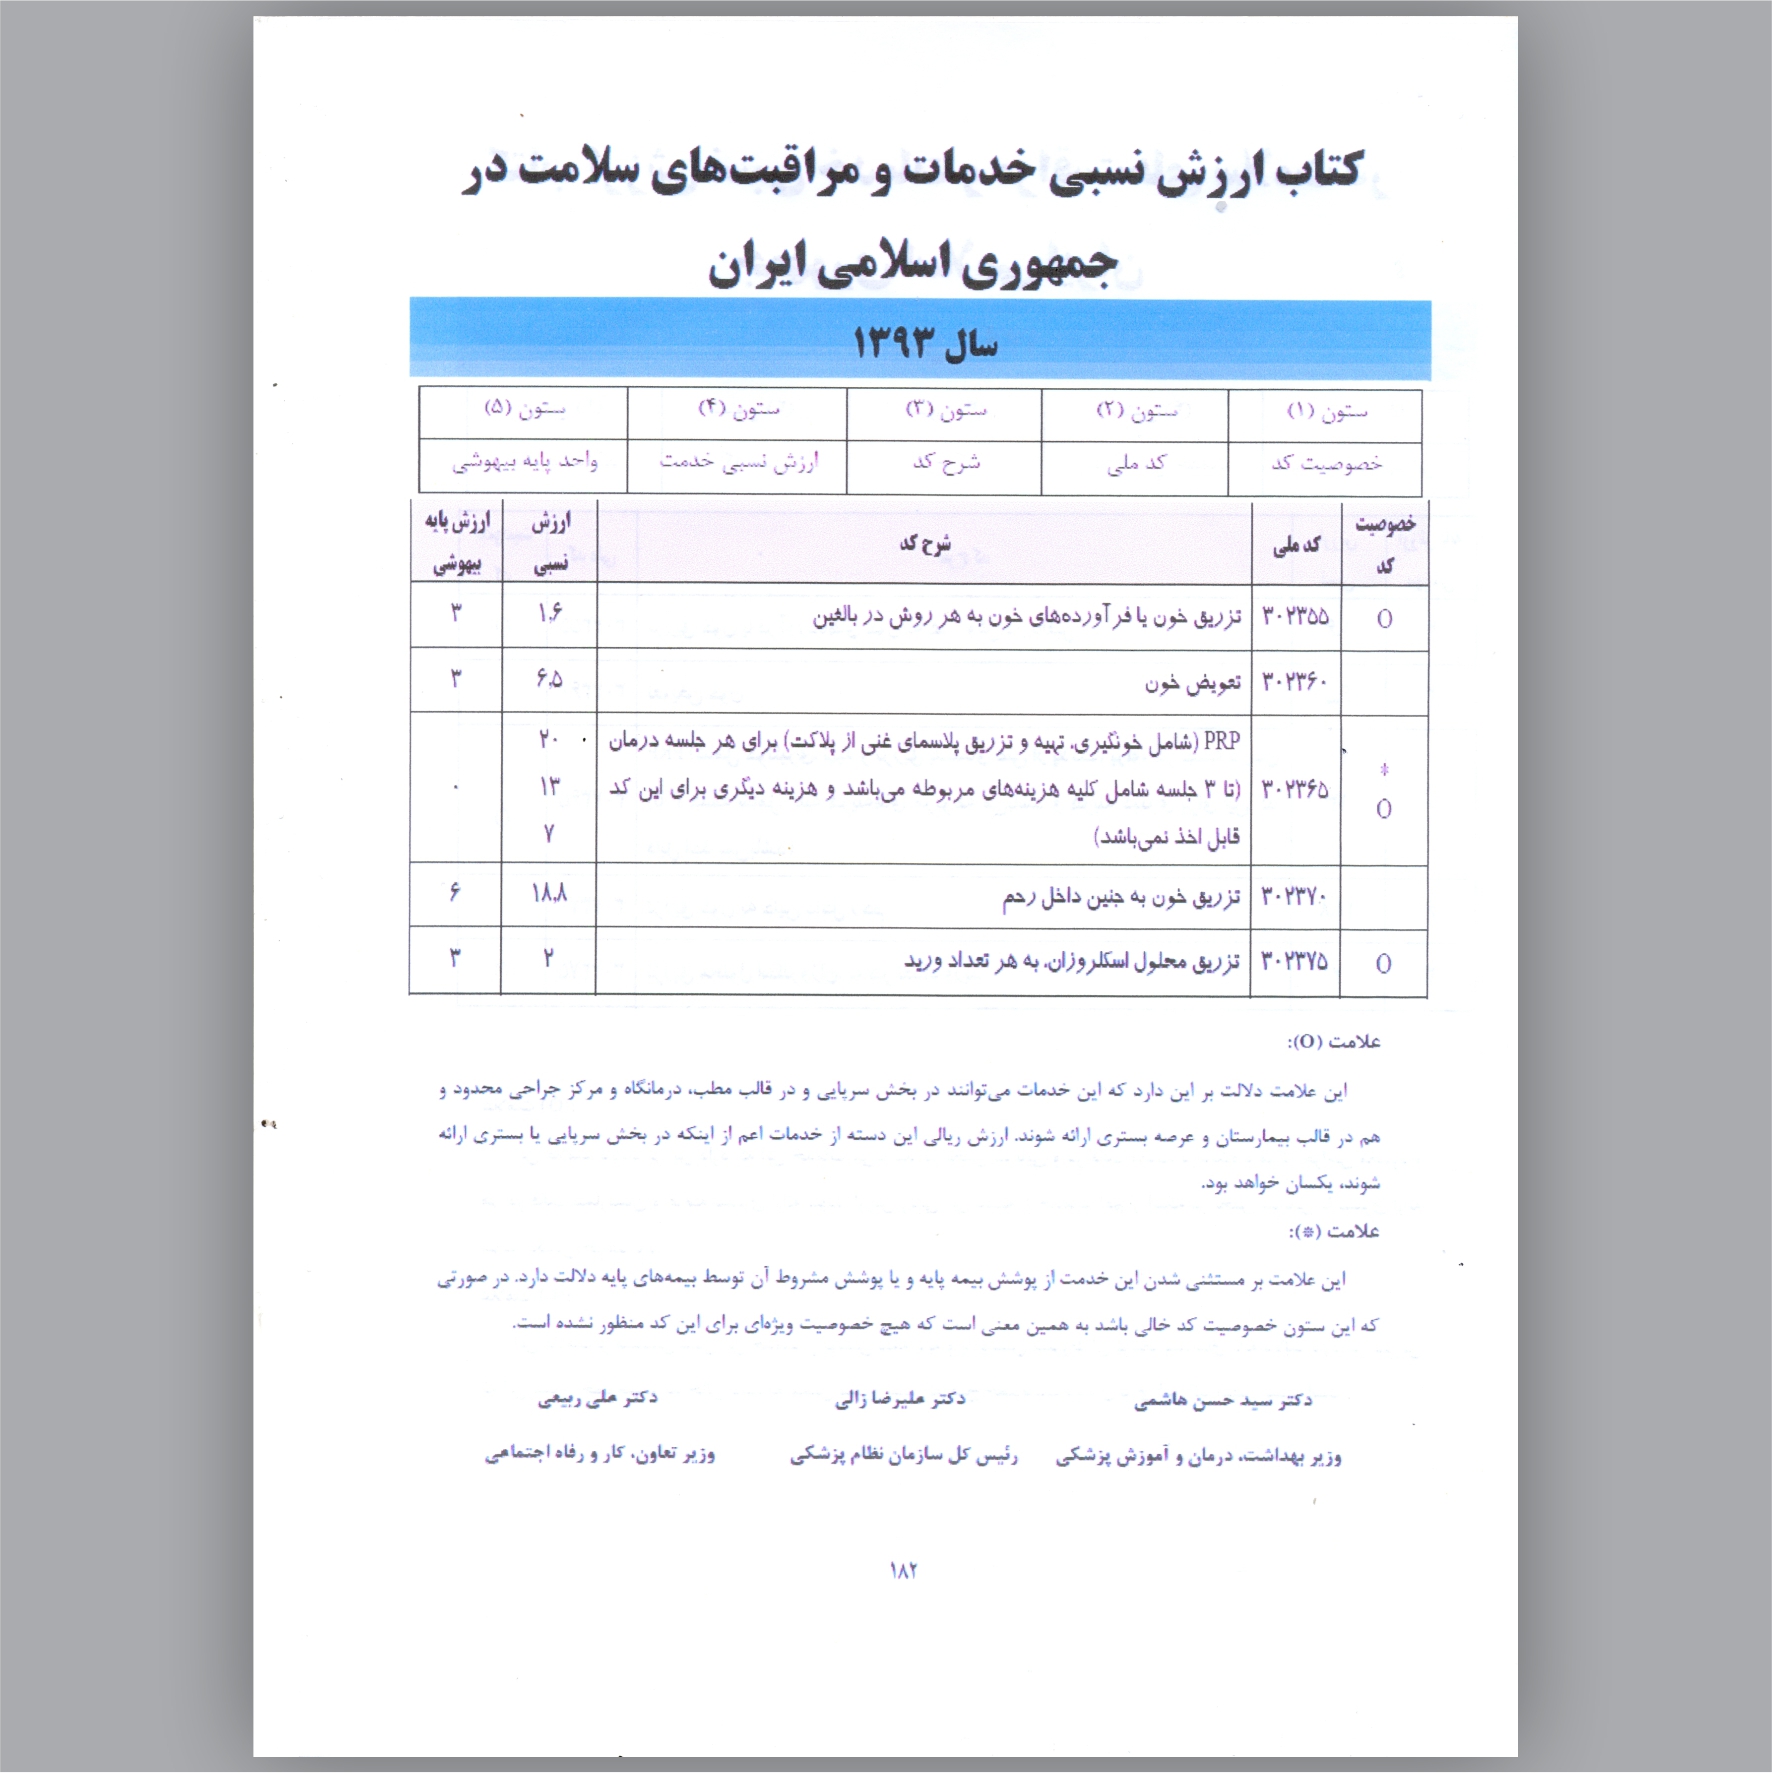

مجوز تولید کیت PRP از وزارت بهداشت ، درمان و آموزش پزشکی-